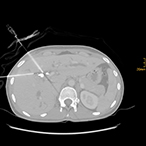

Nach Innsbruck kam Glodny aufgrund eines persönlichen Treffens mit o. Univ.-Prof. Dr. Werner Jaschke, dem Leiter der Innsbrucker Universitätsklinik für Radiologie. „Aus einem zunächst nur kurz angesetztem Termin bei ihm wurde ein mehrstündiges Gespräch, in dem ich erfahren habe, was hier in Innsbruck alles möglich ist und wie ich hier arbeiten kann“, erzählt Glodny rückblickend. Insbesondere die interventionelle Radiologie, durch die vielfältige therapeutische Eingriffe etwa in der Behandlung der arteriellen Verschlusskrankheit, oder von Blutungen oder Aneurysmen, von Tumoren- oder Metastasen möglich geworden sind, fasziniert den Radiologen und Forscher. „Mit durch Hochfrequenzstrom erzeugter Hitze, z. B. dem Verfahren der sogenannten Radiofrequenzablation, können Tumore oder Metastasen in Organen wie Leber, Niere oder Lunge behandelt werden. Die Vorteile dabei sind, dass ein oder mehrere Tumore extrem zielgenau und gründlich zerstört werden können, die ganze Prozedur aber für die Patient:innen sehr schonend ist. Die Absprache mit den behandelnden Kolleg:innen zur Erstellung eines individuellen interdisziplinären Behandlungskonzeptes für jede einzelne Patientin und jeden einzelnen Patienten garantiert die beste Versorgung.“ Am Standort Innsbruck schätzt Glodny vor allem das hohe fachliche Know How und gerät dabei nahezu ins Schwärmen: „Hier wird interventionelle Radiologie in absoluter Perfektion betrieben! Vor allem von Professor Reto Bale, der ein absoluter Experte auch in der Behandlung großer Tumore ist, kann ich sehr, sehr viel lernen. Darüber hinaus ist auch die Zusammenarbeit mit den Kolleg:innen aus der Universitätsklinik für Neuroradiologie unheimlich wertvoll und effektiv.“